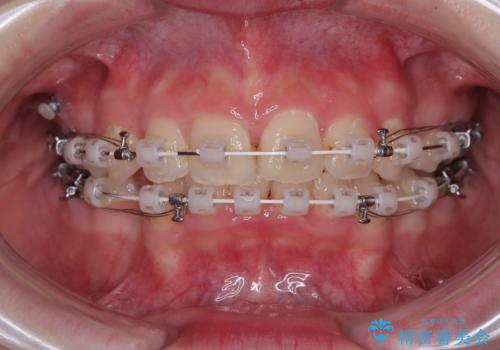

- 審美装置

- 2年

下の前歯が隠れてしまうほど深く咬みこんでいたため、上顎前歯が前方に突出しているような印象がありましたが、咬み合わせが改善され、整った口元に仕上げることができました。